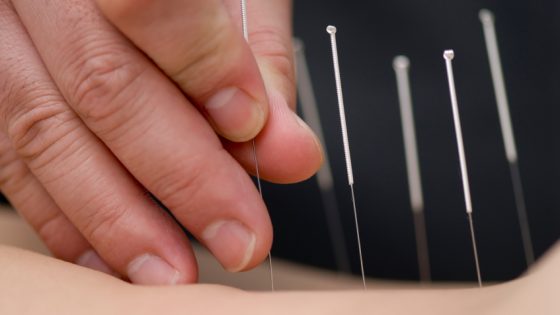

Carolina Paiva, Edição Uma técnica terapêutica milenar que utiliza agulhas, moxas, ventosas, sementes e outros recursos para o tratamento de diversas doenças dos sistemas musculoesquelético, respiratório,...

Sara Abdo A acupuntura aplicada em recém-nascidos e crianças de 0 a 12 anos reduz a cólica, equilibra o sono e estimula a qualidade da amamentação...